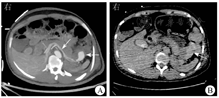

患者女,40岁,主因排"暗红色血便7 d,加重1 d"于2020年10月31日就诊于北京大学第一医院。患者7 d前无明显诱因排暗红色血便伴血块,就诊于某三级甲等医院,行胃镜检查示幽门管溃疡,结肠镜检查示直肠溃疡伴出血可能,但胃镜和结肠镜下皆未见活动性出血,内镜检查后仍有大量鲜血便排出;转诊至另一所三级甲等医院行内科保守治疗,给予200 mL氨甲环酸氯化钠注射液(每100 mL内含氨甲环酸0.5 g、氯化钠0.85 g)止血、4 U悬浮红细胞输注,患者仍间断排鲜红色血便,血红蛋白进行性下降;再转诊至第3所三级甲等医院行肠系膜下动脉+髂内动脉造影术,并予直肠上动脉小分支血管栓塞,后便血再次加重,遂转诊至北京大学第一医院急诊科。急查血常规示白细胞计数为9.56×109/L,红细胞计数为1.84×109/L,血红蛋白为57 g/L,平均红细胞体积为91.8 fL,平均红细胞血红蛋白含量为31 pg,平均红细胞血红蛋白浓度为337 g/L;血生物化学检测示丙氨酸转氨酶为9 U/L,天冬氨酸转氨酶为14 U/L,白蛋白为24.1 g/L,钾离子为3.23 mmol/L;凝血功能检测示凝血酶原时间为13.5 s,活化部分凝血活酶时间为25.8 s,国际标准化比值为1.17,纤维蛋白原为1.38 g/L,D-二聚体为0.29 mg/L;粪便常规检查示镜检红细胞满视野,粪便隐血试验阳性。2020年10月31日21:02行全腹部+盆腔计算机断层扫描(computed tomography,CT)平扫检查示结肠腔内可见稍高密度灶(图1A);胰尾部与结肠间可见一大小为48 mm×43 mm的类圆形病灶,病灶右部呈稍高密度,病灶左部呈稍低密度(图1B);直肠上段可疑增厚,盆腔少量积液。患者自述既往体健,孕2产1,月经规律,无胰腺炎和腹痛病史,未口服抗凝、抗血小板药。体格检查示体温为36.7 ℃,血压为117/71 mmHg(1 mmHg=0.133 kPa),心率为96次/min,呼吸频率为16次/min;神志清楚,精神可,贫血貌,腹软无压痛,无腹膜刺激征,肝、脾肋下未及,肠鸣音8次/min,墨菲征阴性,移动性浊音阴性。